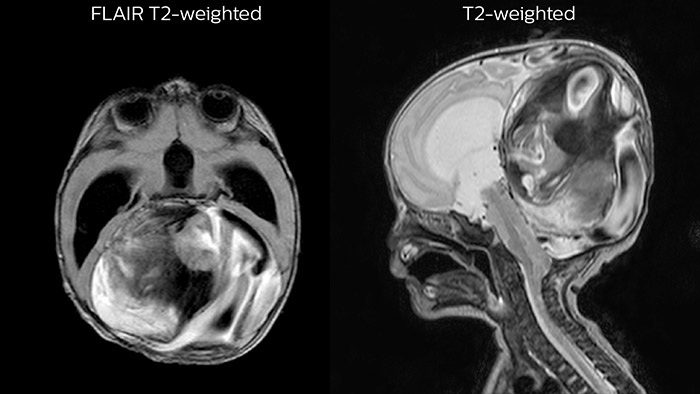

Dural sinus malformation (DSM) Initial examination

After three times of coiling and acryl based embolization

Hydrocephalus post hemorrhagic Both pictures show a ventriculoperitoneal shunt. With our previous scanner our hydrocephalus protocol needed about 25 min. With Ambition the examination time is about 14 min. including a CSF PCA sequence to show flow in the aqueduct.